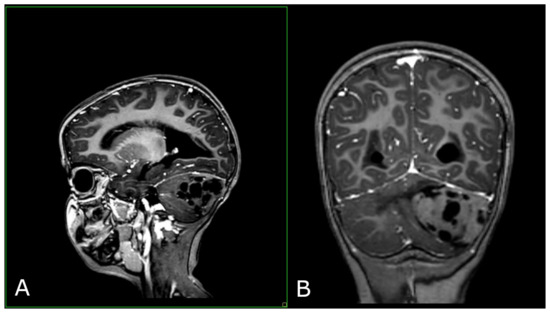

- Frontal Plane: Detailed video properties were provided (FPS, number of frames, duration, and dimensions);

- Sagittal Plane: Detailed video properties were not provided;

- Sagittal Plane: The focus was on image content analysis, brightness and contrast, object detection, and temporal analysis;

- Frontal Plane: The results indicated regions of motion and contour analysis;

- Sagittal Plane: The results included brightness and contrast analysis and edge detection;

- Frontal Plane: The model could not clearly recognize the medical context, suggesting motion and contour analysis;

- Sagittal Plane: The model suggested a medical imaging context and tumor detection based on context and image analysis.